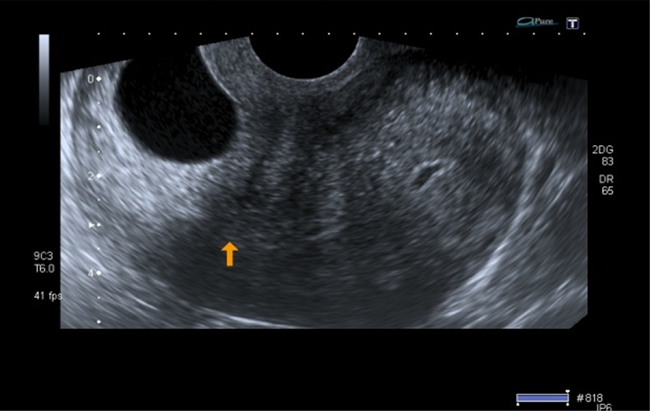

A la paciente se le realizó una prueba en sangre para cuantificar la fracción beta de la gonadotrofina coriónica humana (Abbott Laboratories. Architect.B-hCG Total), que se reportó en 31.819 mUI/ml. También se le tomó una ecografía endovaginal (Toshiba-Xario XG) que mostró la presencia de útero con medidas de 72 × 52 × 54 mm con un cuello de 35 mm con orificio interno cerrado. El endometrio midió 18 mm, sin evidencia de saco gestacional intrauterino y en la región ístmica y cervical, por debajo de las arterias uterinas, se encontró un saco gestacional de 30 mm con presencia de embrión único de 20,6 mm sin presencia de actividad cardiaca fetal (figuras 1 a 4).

Figura 4 Orificio cervical interno cerrado (flecha amarilla), debajo del cual se evidencia la implantación del saco gestacional en la mucosa cervical